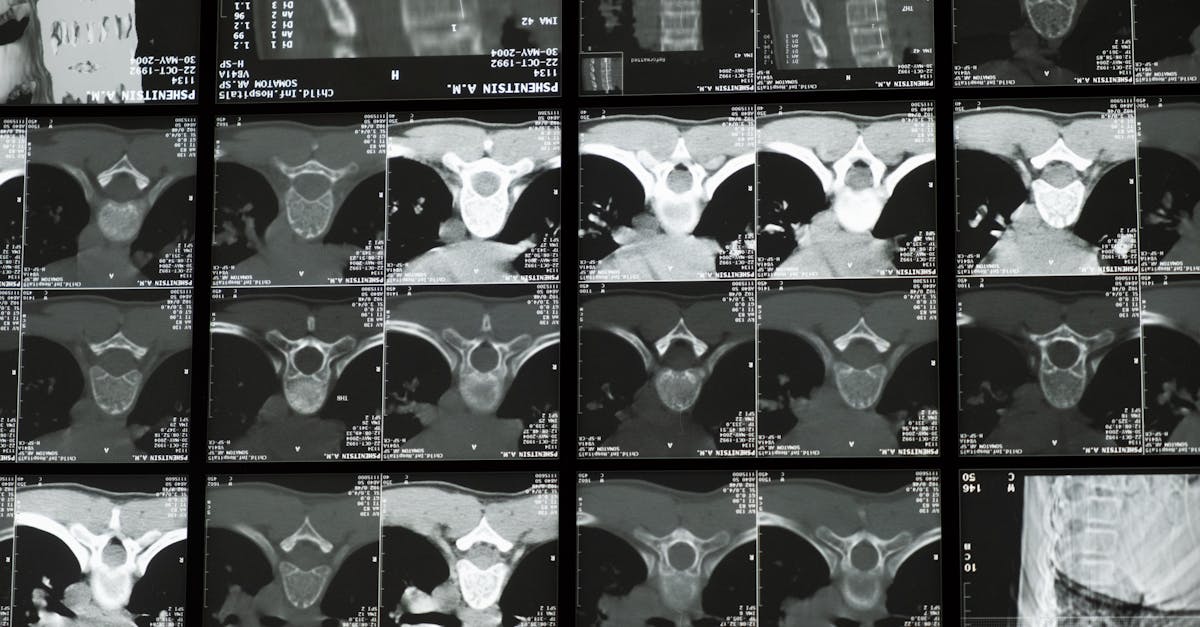

Artificial Intelligence (AI) and Clinical Decision Support Systems (CDSS) are merging to create powerful tools that profoundly assist orthopedic specialists. These systems analyze vast datasets, including patient demographics, detailed medical history, imaging results (X-rays, MRIs, CT scans), and even genetic markers, to identify intricate patterns and predict potential outcomes with remarkable accuracy. This level of EMR analytics care empowers our doctors with deeper clinic data insights, leading to more accurate diagnoses and highly personalized treatment plans. Imagine a system that can flag potential complications based on a patient’s unique biomechanical profile or suggest optimal surgical approaches by analyzing thousands of similar successful cases. This proactive capability allows us to intervene earlier, refine treatment strategies, and significantly improve surgical success rates and rehabilitation outcomes.

One of the most significant benefits of AI CDSS is its unparalleled ability to augment diagnostic accuracy, particularly in complex orthopedic conditions where symptoms can be ambiguous or overlap. By meticulously cross-referencing patient symptoms, imaging findings, lab results, and an ever-growing comprehensive knowledge base of medical literature, these systems can suggest differential diagnoses that might be overlooked. They can detect subtle fractures, early signs of degenerative joint disease, or even rare musculoskeletal conditions that require specialized attention. For our orthopedic clinics, this means a reduced margin for error and a consistently higher standard of care for every patient. This advanced capability is not about replacing the clinician’s expertise but rather empowering them with an intelligent assistant that processes and correlates information at speeds and scales impossible for humans alone, allowing our doctors to focus on the human element of patient care.

- A: AI CDSS analyzes patient demographics, medical history, physical examination findings, detailed imaging (X-rays, MRIs, CTs), lab results, and even surgical notes to provide comprehensive insights and recommendations.